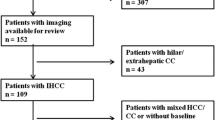

The study population included 88 patients with histological diagnosis of ICCs: 61 with mass-forming type, 23 with periductal-infiltrating tumours and 4 with intraductal-growing type. As a control study groups, we identified: 86 consecutive patients with liver colorectal intrahepatic metastases (mCRC) (groups A); 35 consecutive patients with peribiliary metastases (groups B); 62 consecutive patients (groups C) with hepatocellular carcinoma (HCC); 18 consecutive patients (groups D) with combined hepatocellular cholangiocarcinoma (cHCC-CCA); and 26 consecutive patients (groups E) with hepatic hemangioma. For all lesions, magnetic resonance (MR) features were assessed according to Liver Imaging Reporting and Data System (LI-RADS) version 2018. The liver-specific gadolinium ethoxybenzyl dimeglumine—EOB (Primovist, Bayer Schering Pharma, Germany), was employed. Chi-square test was employed to analyse differences in percentage values of categorical variable, while the nonparametric Kruskal–Wallis test was used to test for statistically significant differences between the median values of the continuous variables. However, false discovery rate adjustment according to Benjamin and Hochberg for multiple testing was considered.